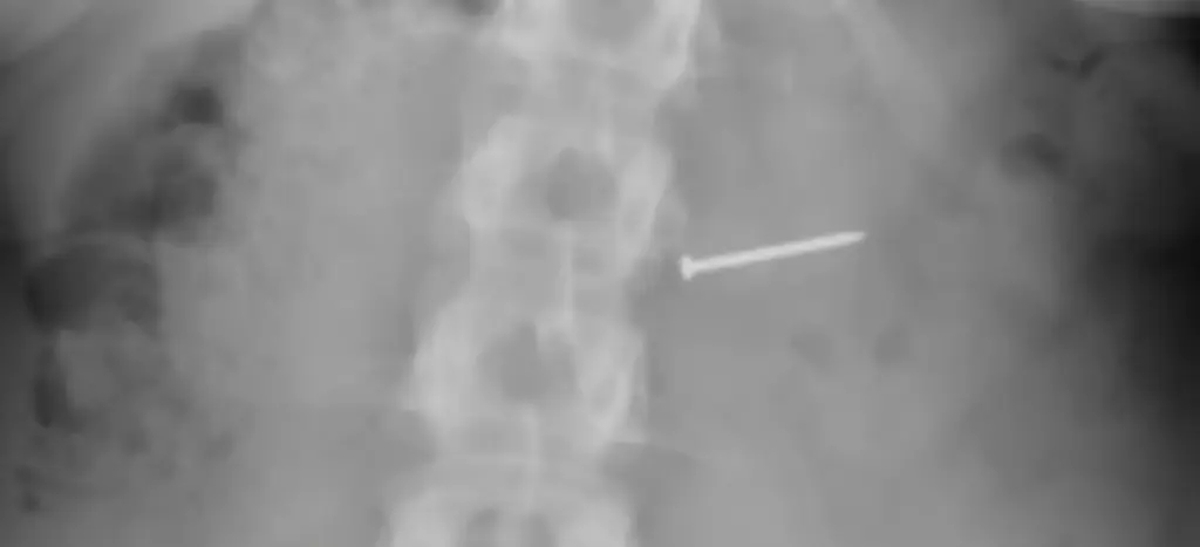

2018-buckley-told-wesh-2-124626273.jpg엑스레이 사진에서 금속 못이 몸속에 박힌 것이 확인되었다. / 뉴욕포스트